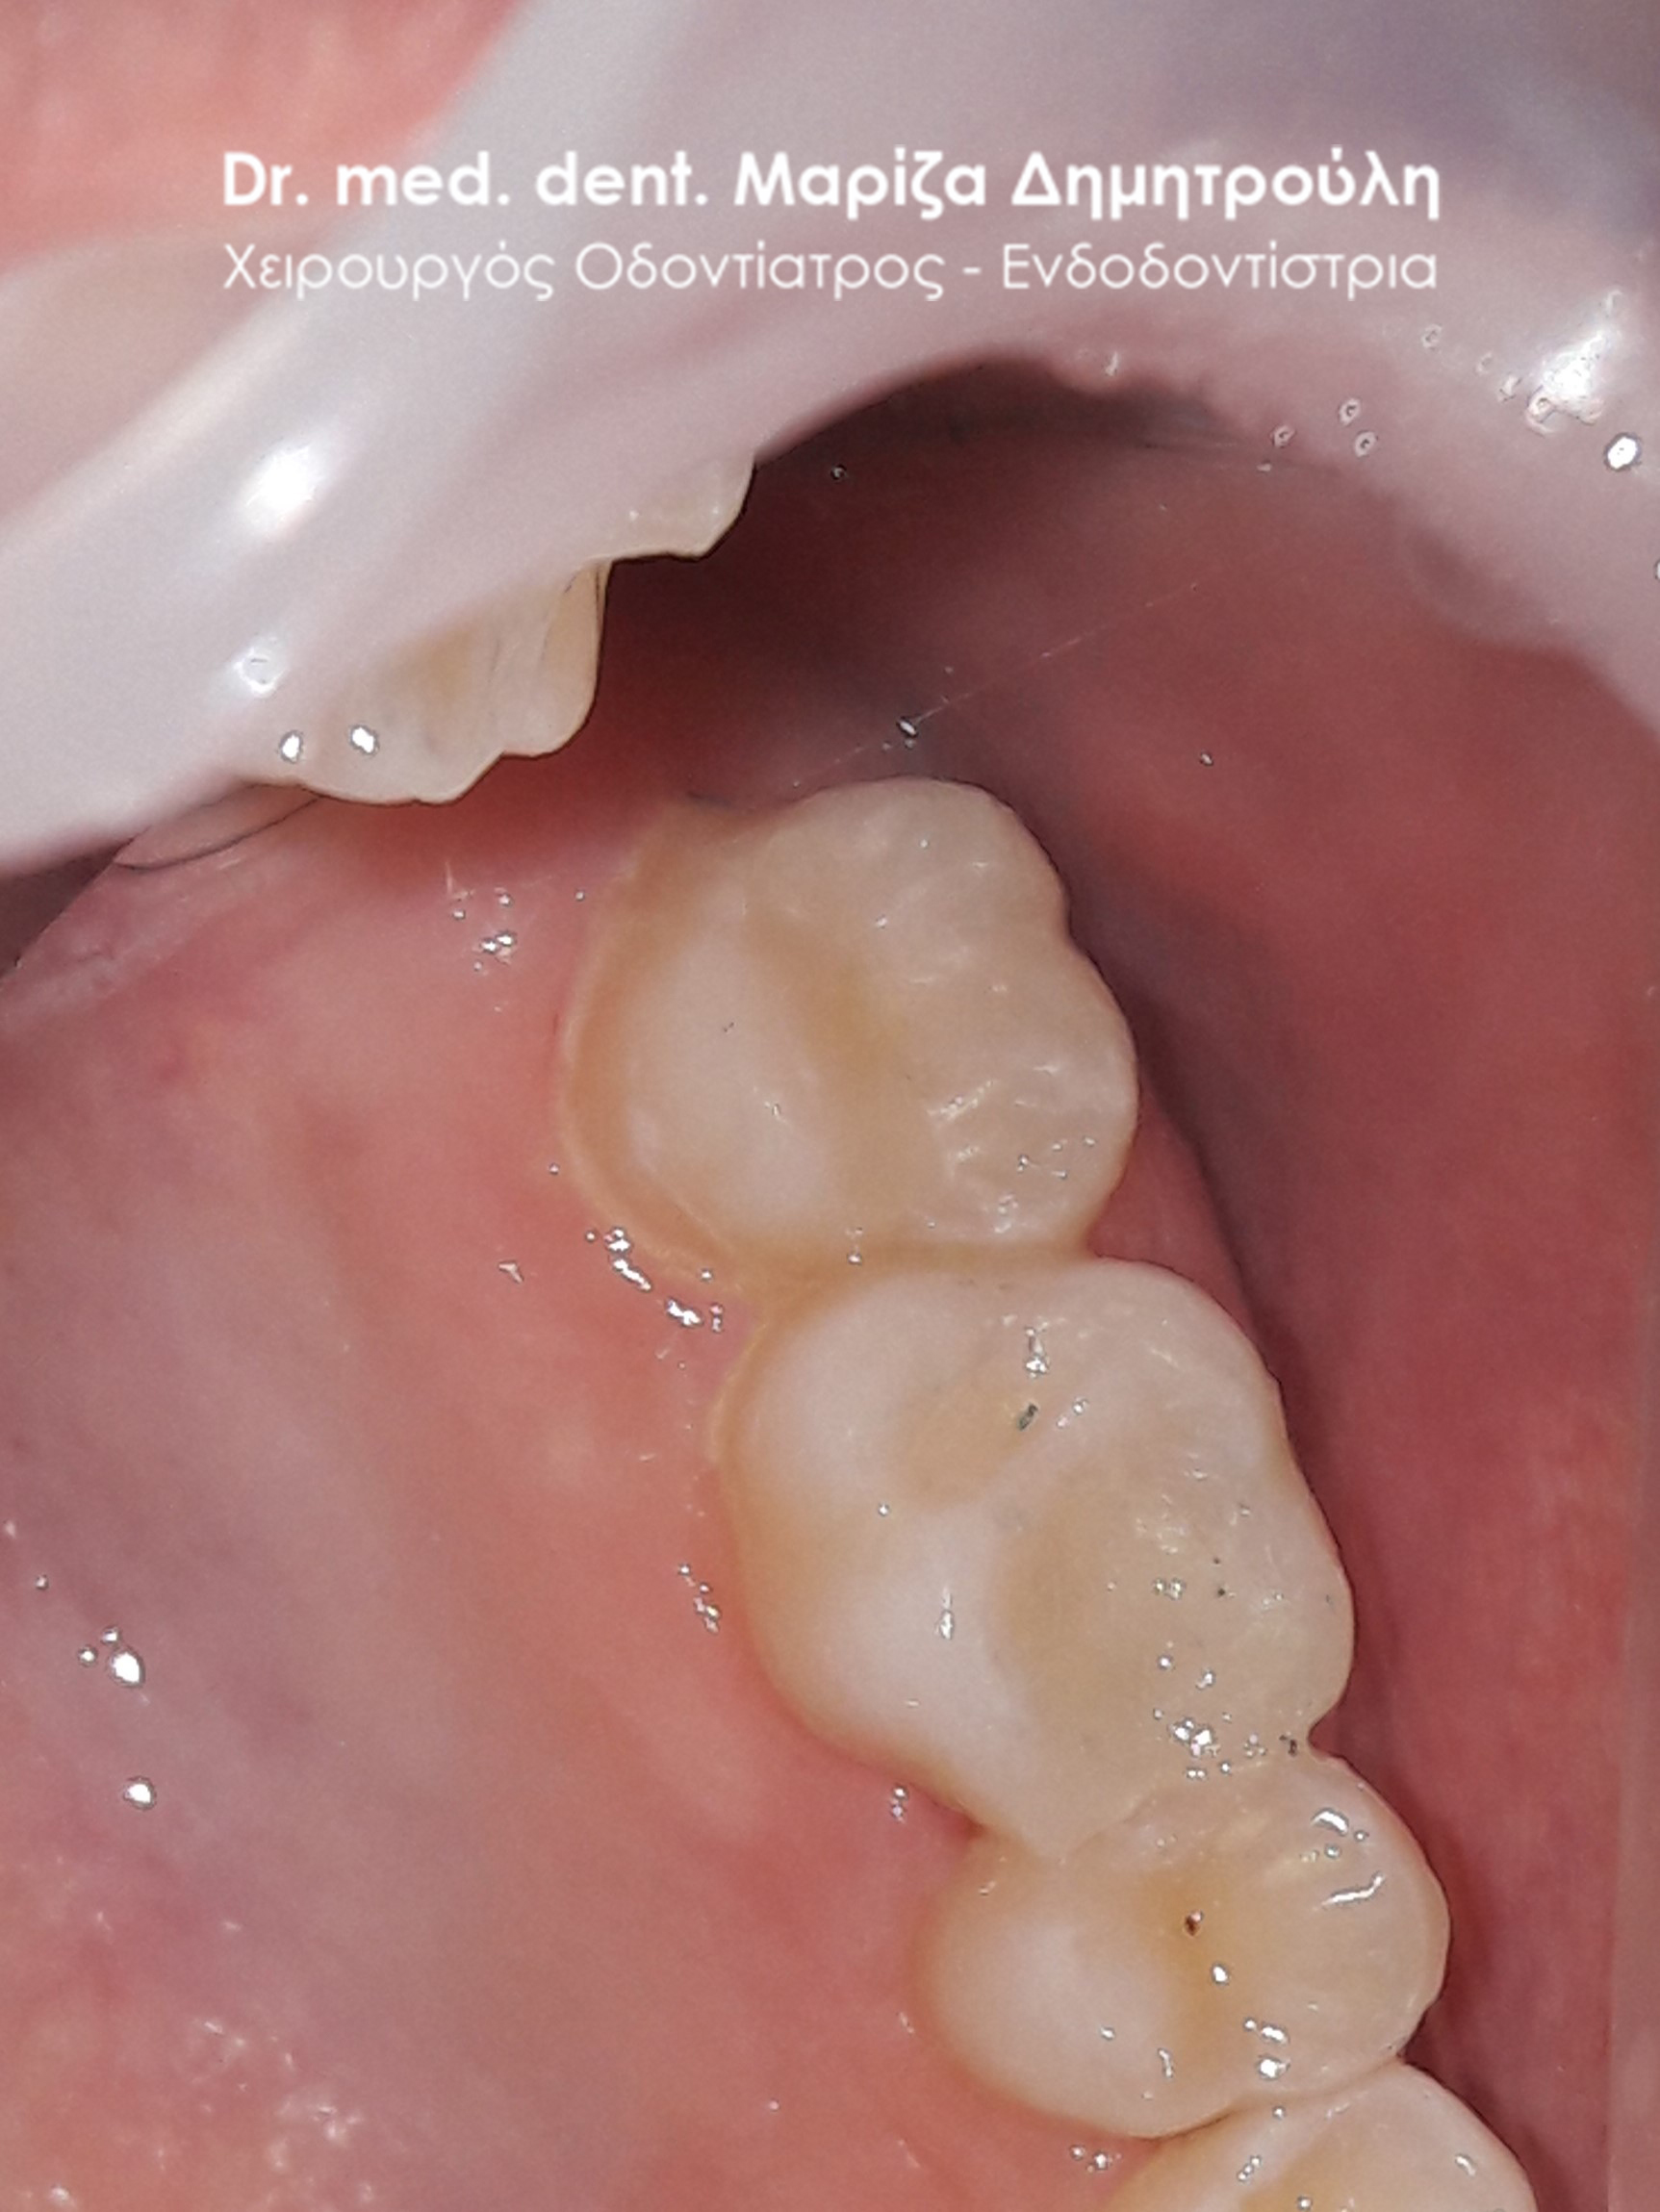

Περιστατικό – Αντικατάσταση σφραγισμάτων δοντιών

Ο ασθενής επιθυμούσε την αντικατάσταση των παλιών μαύρων σφραγισμάτων αμαλγάματος με λευκά σφραγίσματα σύνθετης ρητίνης.

Η θεραπεία πραγματοποιήθηκε με τη χρήση ελαστικού απομονωτήρα, όπως ορίζουν τα παγκόσμια πρωτόκολλα οδοντιατρικής για την αφαίρεση των μαύρων σφραγισμάτων. Οι οδοντίατροι θα ήταν καλό να χρησιμοποιούν απομονωτήτρα κατά την αφαίρεση σφραγισμάτων αμαλγάματος, έτσι ώστε ο ασθενής να εισπνέει ελάχιστα και να μην καταπίνει τον υδράργυρο, που απελευθερώνεται κατά τη διαδικασία αυτή.

Το σχέδιο θεραπείας του πρώτου γομφίου (δόντι με πολύ λευκό σφράγισμα) ήταν υπό συζήτηση, γι΄ αυτό και η αποκατάσταση του δοντιού με προσωρινό σφράγισμα.

ΠΡΙΝ

META